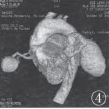

图4 VRT重组图像清晰显示供血动脉、引流静脉及扩大的畸形血管团